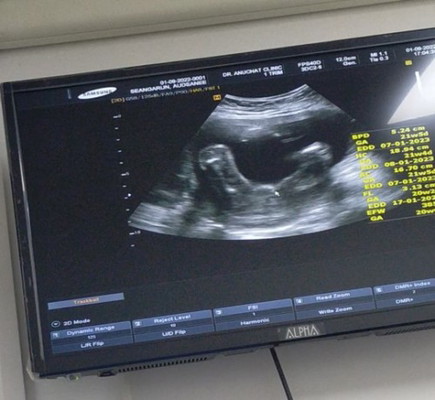

แม่ๆดูให้หน่อยค่ะ แบบนี้ผู้หญิงรึผู้ชายค่ะ

คุณหมอบอกผู้หญิง70% อีก30% มีโอกาสผิดพลาดไหมค่ะ😂

น่าจะไม่พลาดนะคะ เห็นชัดเลย😁